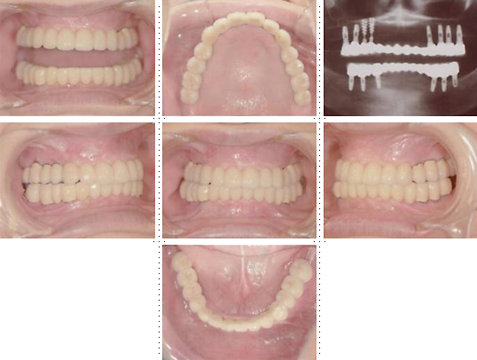

症例1

58才 女性

嘔吐反応が激しく入れ歯を入れると気持ち悪くなってしまうと、インプラント希望で来院されました。

上顎左右奥に4本ずつ計8本のインプラント埋入。下顎左右奥に3本ずつ計6本のインプラント埋入上下顎とも全体的にセラミックを使用した冠をセット。